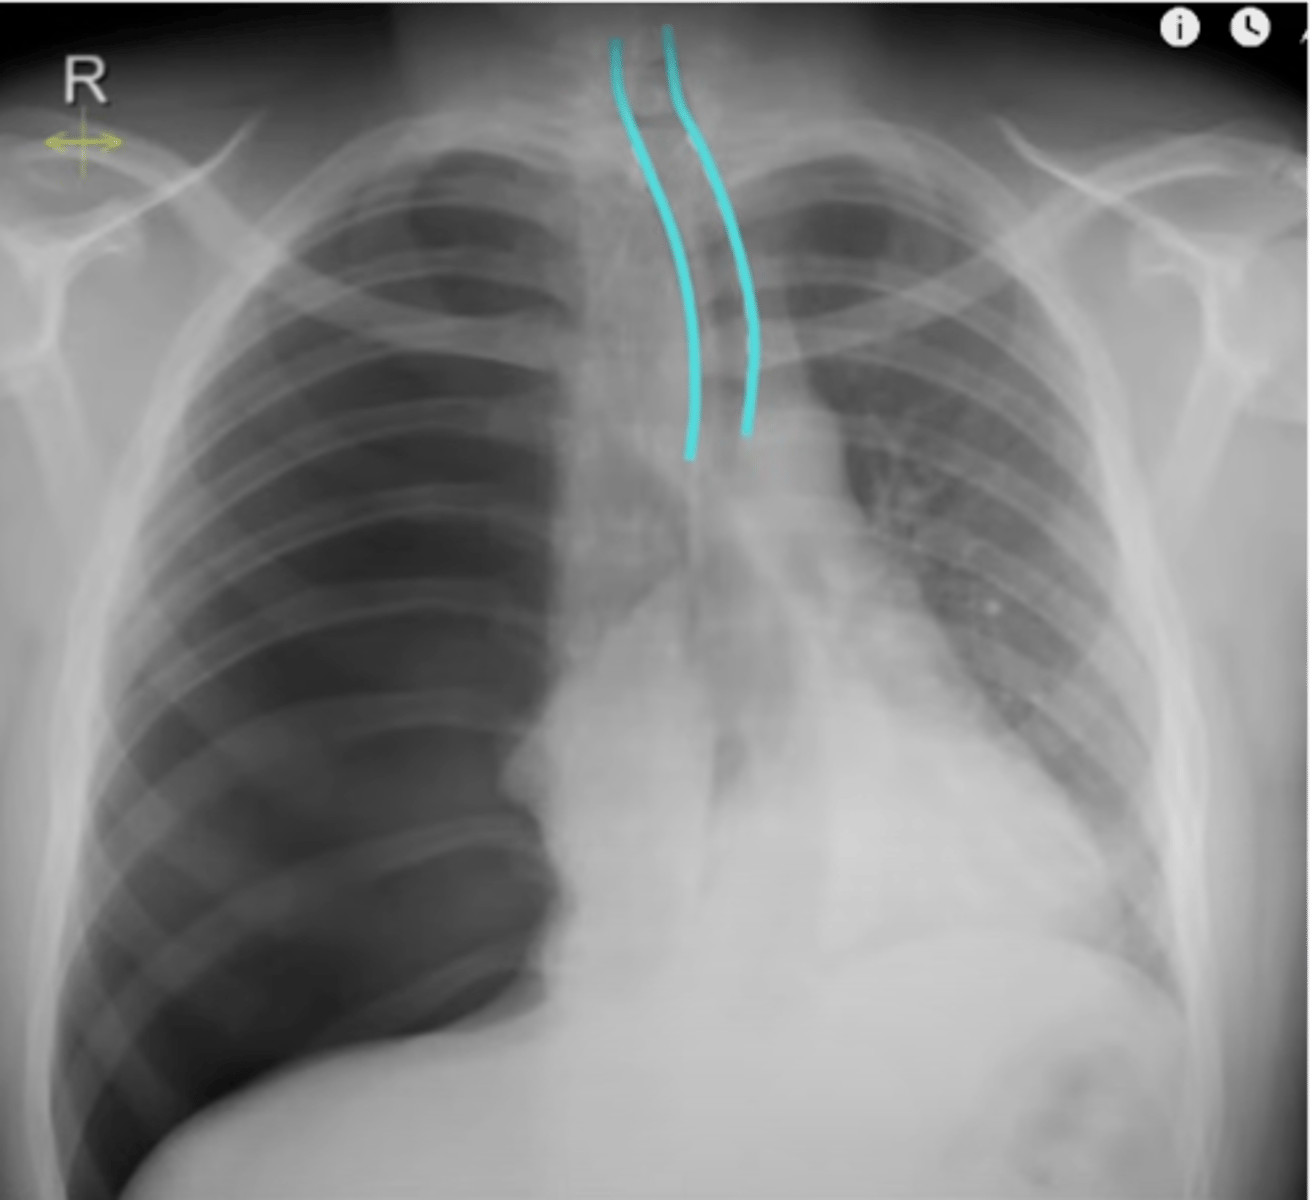

-rotation: is the XR straight or at an angle?

-spine should be vertical, clavicles should be equidistant from spine

What does the R stand for in RIPE